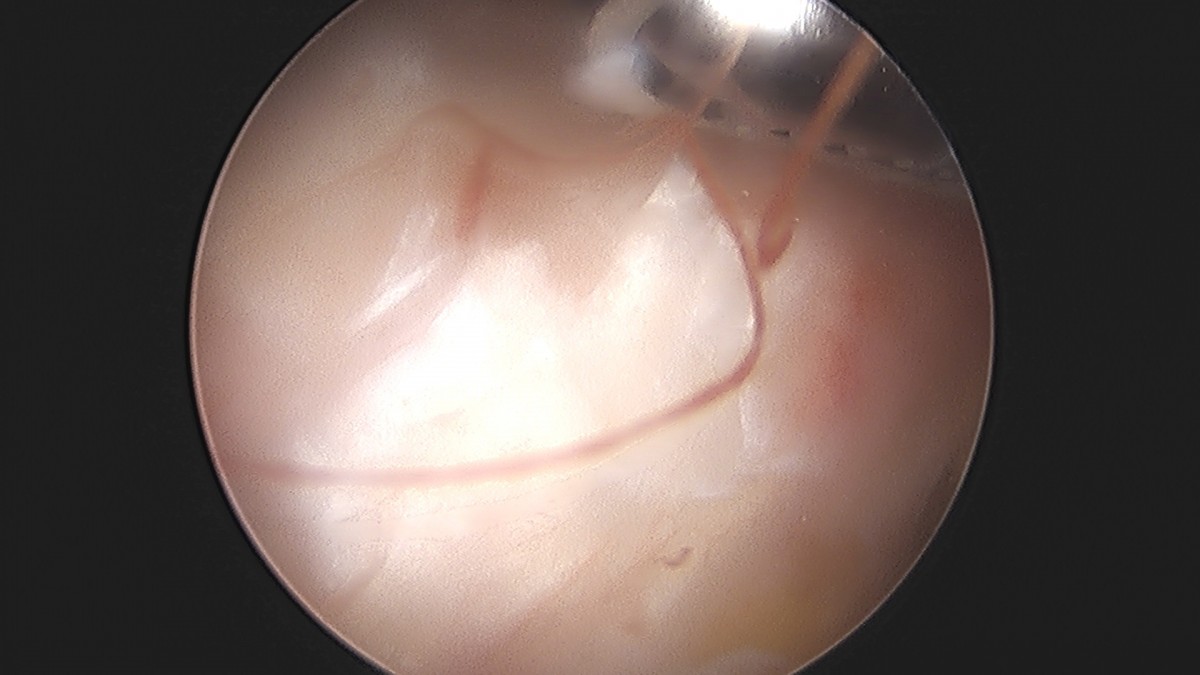

이재상원장님 어깨 견봉하 감압술 및 석회 제거술 이형O 환자

작성자 최고관리자 댓글 0건 조회 746회 작성일 25-09-16 15:40